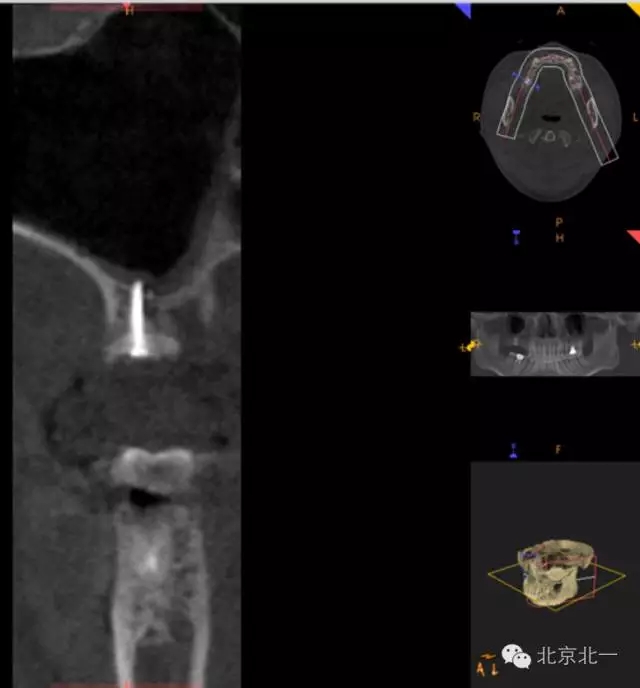

圖十九:手術(shù)后當(dāng)天CBCT

圖二十-二十二:ONLAY植骨半年后

圖十三:取出螺釘。

圖十八:手術(shù)前CBCT